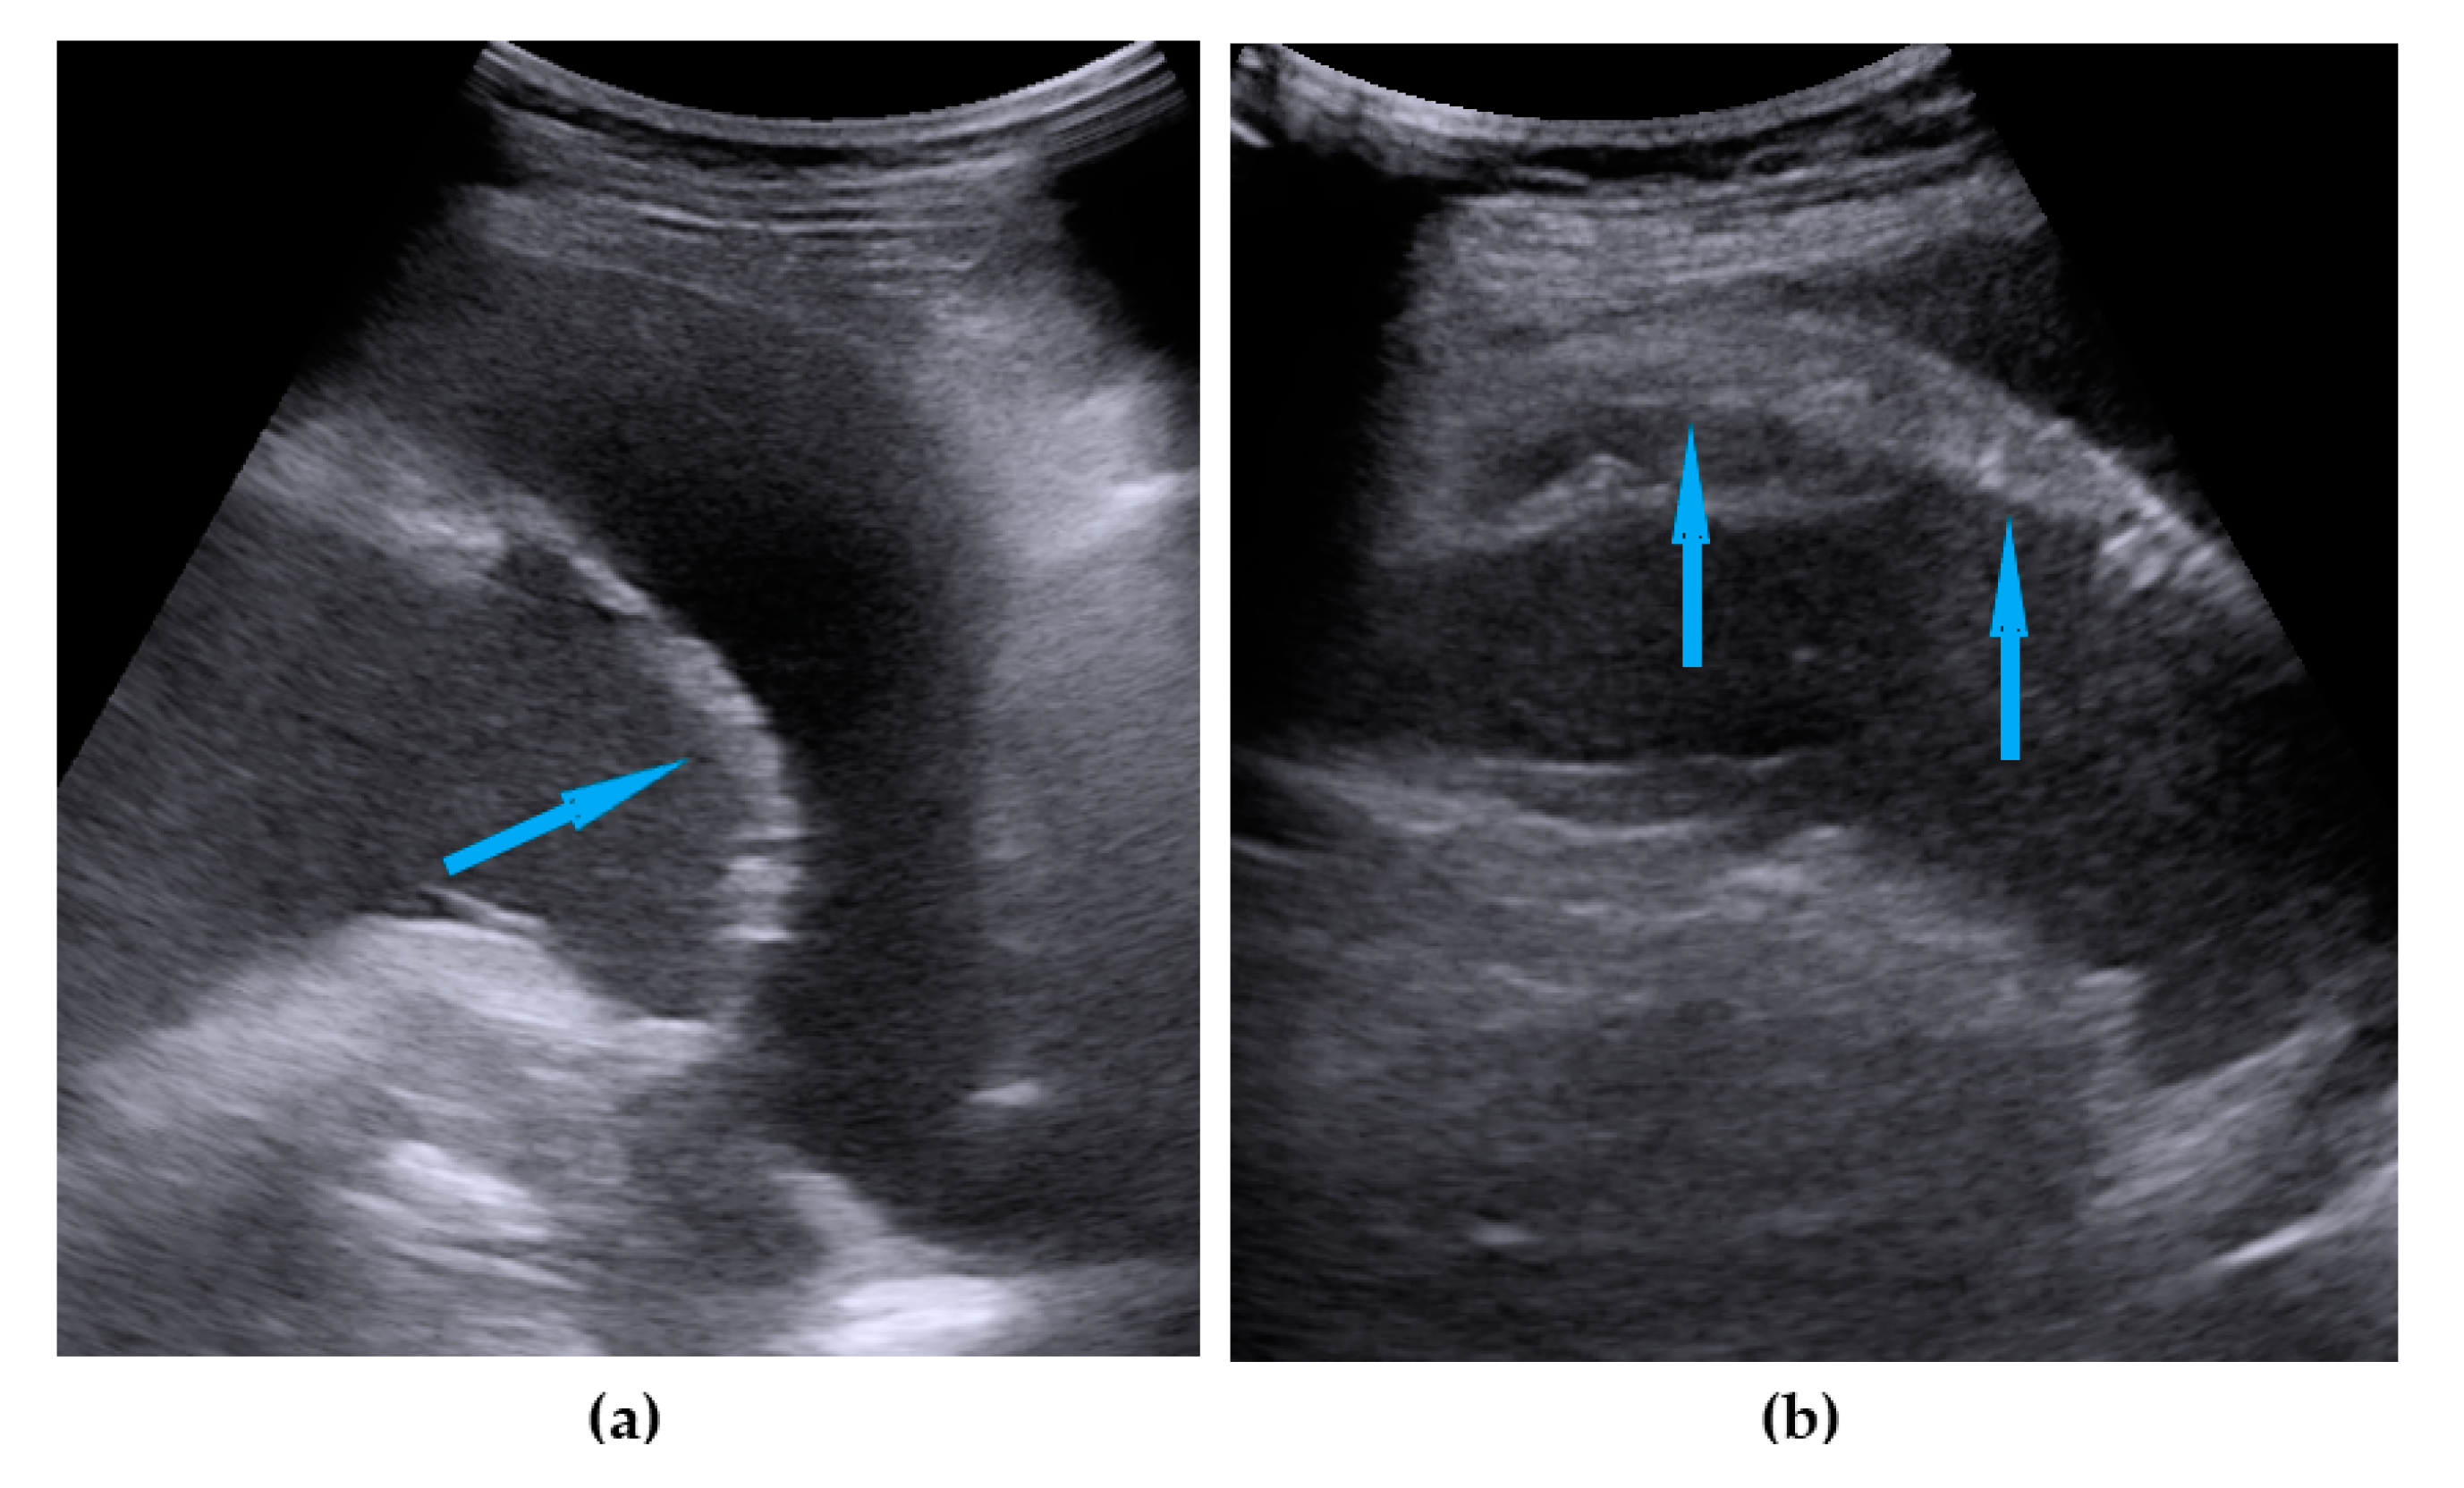

| Spleen, hilum | Presence of nodules or rigid structures in the region of the spleen hilum. | Figure 9 | Video S9 |

| Diaphragm, right | Carcinomatosis manifests as hypoechogenic lesions over the peritoneal surface of the right diaphragm. | Figure 10 | Video S10 |